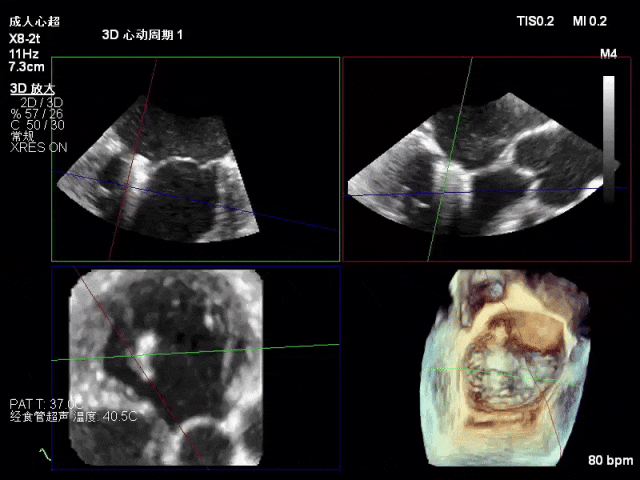

术前心超

二尖瓣前叶脱垂,功能性二尖瓣反流(FMR),新分型:DAA型

A2瓣叶脱垂、瓣尖对合错位,反流2区,MR 4+,VC:5×12mm

术中超声(关键步骤)